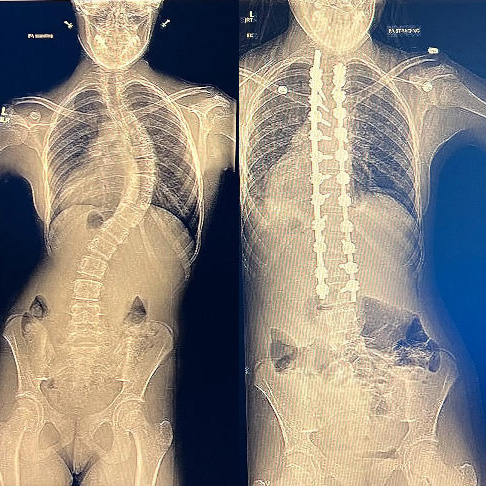

Hi! My name is Aarushi Sheth and I was diagnosed with Adolescent idiopathic scoliosis of thoracolumbar region when I was 12, during the summer of 2020. It started with a routine check up with my pediatrician, where the doctor told me I had scoliosis. He told me that it didn’t look serious and is mainly common among girls my age, but recommended for me to go get an X-Ray just in case. After getting my X-Ray I found out the severity of the situation, the curve of my spine was bad enough that I immediately had to consider bracing or surgery.

Bracing was supposed to be good enough to help me, so I went with that. Soon after I made my choice I immediately had to go to another specialist who prepared me for my brace. A couple weeks later I obtained my back brace and started wearing it. I constantly felt uncomfortable and hated wearing it. I felt like I couldn’t breathe, and when I had to wear it out I always felt weird and uncomfortable. During this time my mental health got very bad, I felt different then every one else and so unhappy that this was happening to me. I stopped doing the sports I was in, stopped going to sleepovers, and overall became a shell. Over time my feelings about the brace got better, especially with my friends’ help, but during my two years of bracing my curve got worse. This is because I had another condition that caused my scoliosis called Chiari Malformation specifically type 2. Due to this I got my first surgery and when I went to my next back appointment I found out that my curve was so bad I had to get surgery.

So the summer before my freshman year when I was 14 I got the surgery. I was very scared at the time, but now I have no regrets. Recovery isn’t easy, I won’t lie, during that time I was in a lot of pain and couldn’t always do everything I wanted, but now the back that once kept giving me pain barely hurts. I no longer have a curve, and with my surgeons I am able to do so much. Currently I am an active member of many of my school’s clubs, I exercise and practice taekwondo, where I am training for black belt testing, and I enjoy the things I always felt I never could prior. I am proud of myself for doing what I did, and as a senior in High School now I have no regrets- bracing and surgery really worked out for me. For all those struggling there is a light at the end of the tunnel, and if you ever need anything don’t be scared to share!